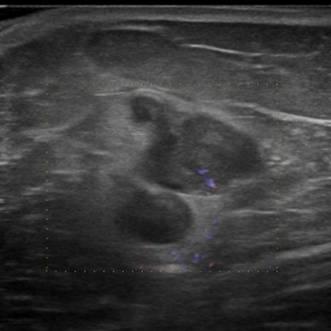

Di căn vú

» Thông tin: Nữ giới – 70 tuổi.

» Lâm sàng: Khối tuyến vú / K hắc tố.